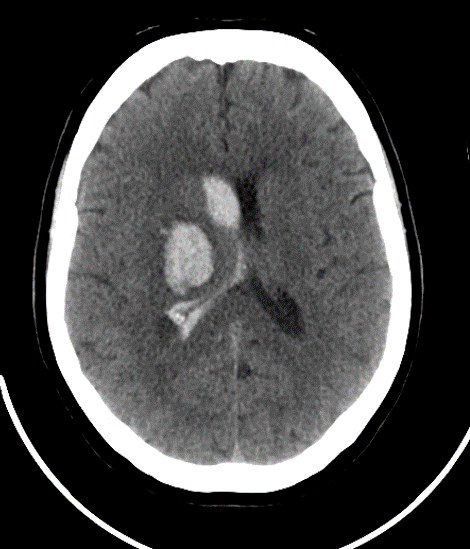

What type of stroke is shown ?

Haemorrhage stroke